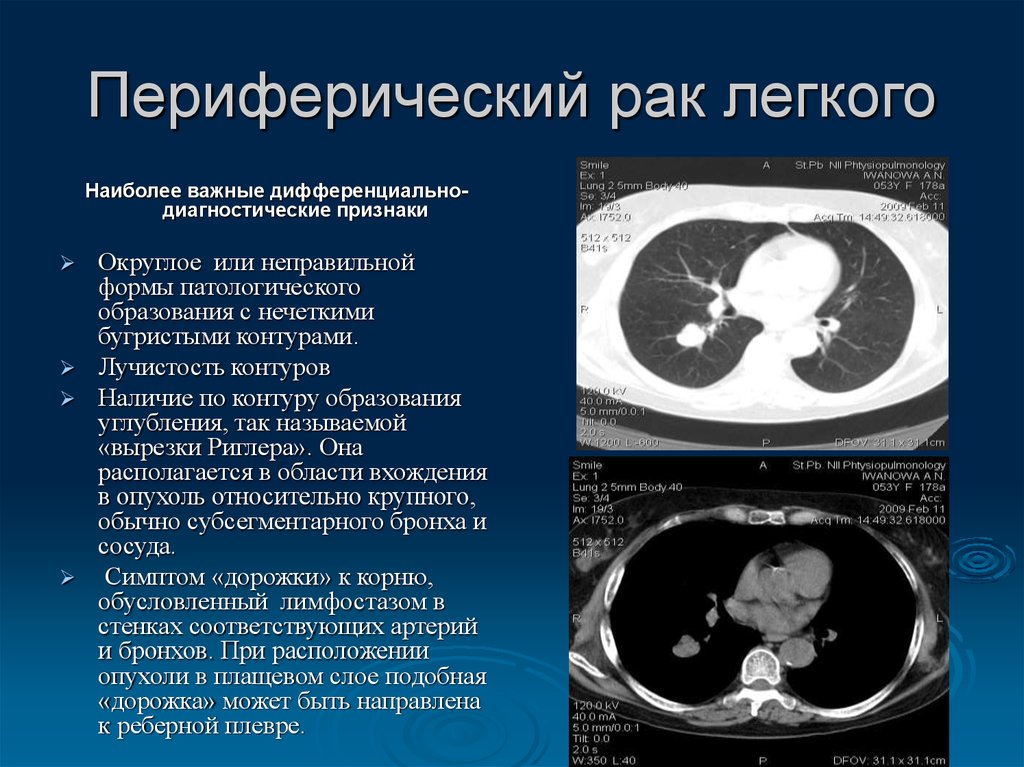

Хирургическая операция. Эндоскопическая операция. Хирургическое вмешательство. Эндоскоп хирургический. Периферическая карцинома легких кт. Периферический очаг легкого. Кт признаки периферического. Периферическое новообразование.

Периферическая карцинома легких кт. Периферический очаг легкого. Кт признаки периферического. Периферическое новообразование. Магнитно-резонансная томография легких. Магниторезонансная томография легких. Магнитно ядерная томография. Ядерно-магнитно-резонансная томография.